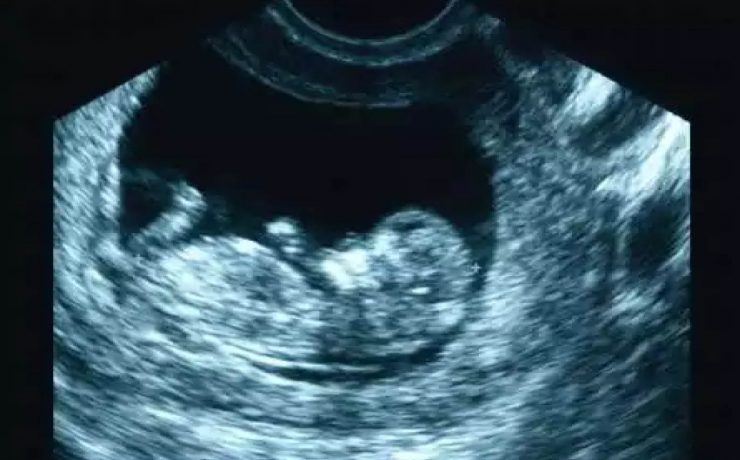

EL MODO A (modo de amplitud) fue el primer método utilizado para formar imágenes de ultrasonido. EL MODO B: modo de brillantez MODO M: modo de movimiento. Tiene su utilidad principal en ecocardiografía tanto en la fetal como en la del adulto. MODO B.- imagen en tiempo real. Al mover